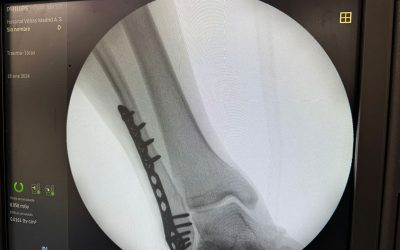

Prótesis de tobillo: alivia el dolor y recupera movilidad

Sep 27, 2024

Con un caso concreto del Dr. David Cimas vemos cómo una prótesis de última generación devolvió la funcionalidad a un...